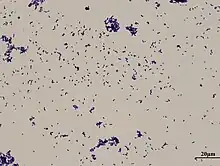

| Gram stain of Corynebacterium xerosis | |

Corynebacterium xerosis is a Gram-positive, rod-shaped bacterium in the genus Corynebacterium. Although it is frequently a harmless commensal organism living on the skin and mucus membranes, C. xerosis is also a clinically-relevant opportunistic pathogen that has been attributed to a number of different infections in animals and humans.[1][2] However, its actual prominence in human medicine is up for debate due to early difficulties distinguishing it from other Corynebacterium species in clinical isolates.